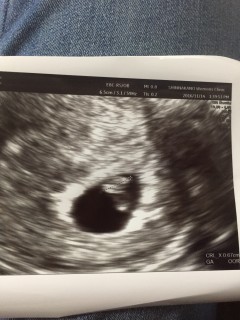

ずっと胎嚢しか見えてなくて今回も見えなかったら?と不安で一杯でしたが無事写ってくれて、心臓の動きも確認とれました。5.8と小さめみたいですが逢えました。

6w4d6mm 少量の出血があったり下腹部痛があったけど、異常なしで安心した!これからもすくすく育ってね

少量の出血があり不安で病院へ。。 心拍確認出来ました!! 初めての妊娠でまだまだ不安ですが。。 一安心